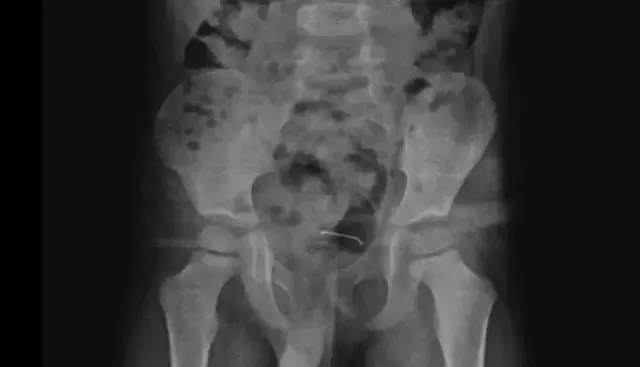

Olay Bitlis'in Güroymak ilçesinde yaşandı. Sürekli karnı ağrıyan 5 yaşındaki çocuk ailesi tarafından çeşitli sağlık kuruluşlarına götürüldü. Sonuç alamayan aile, küçük çocuğu en son Tatvan Devlet Hastanesi'ne götürdü. Çekilen röntgende çocuğun mesane duvarında metal bir cisim olduğu ortaya çıktı.

9 ay önce yutulan ve vücutta kalan 3 santimetrelik toplu iğnenin mesane duvarına yapıştığı anlaşılınca ameliyata karar verildi.